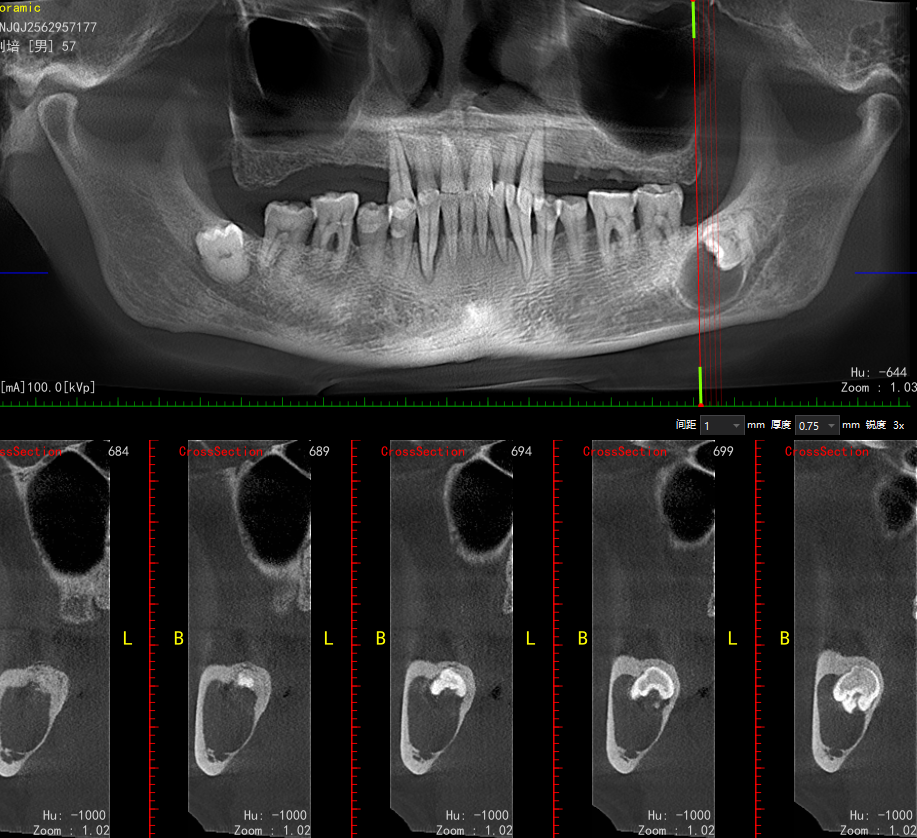

智齿含牙囊肿

门诊手术增加了难度,还是收住院稳妥点